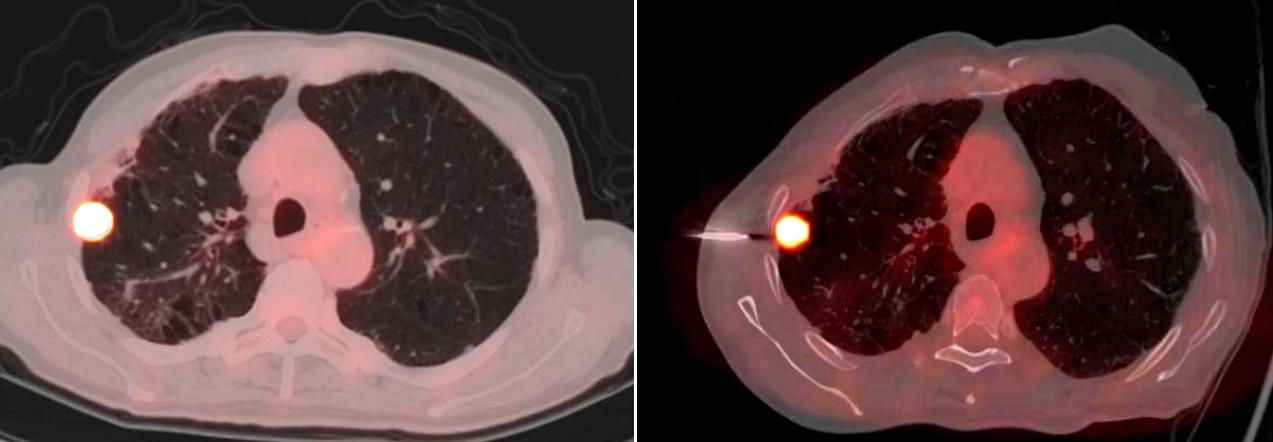

手术当日,PET/CT中心的方龙栋主管技师首先为患者进行了详细的扫描,精准确定了肿瘤的位置和代谢活跃区域。随后,在胸外科医生严密的监测下,精准地将穿刺针经皮穿刺进入患者肺部,准确抵达肿瘤部位,成功获取了病理组织样本。整个手术过程顺利,患者术中及术后均未出现明显并发症。从PET/CT的精准成像,到胸外科医生的穿刺操作,再到病理科的准确诊断,体现了胸外科、PET/CT中心、病理科多学科团队的高效配合和专业能力。

精准定位:PET/CT融合了PET的功能代谢信息和CT的解剖结构信息,不仅能清晰显示肺部结节、占位的形态、大小、位置等解剖特征,还能通过代谢情况准确区分肿瘤组织与周围正常组织、炎性病变等。对于一些在常规CT上难以准确判断边界或性质的微小肺结节、位置特殊的肺占位,通过PET显示病变代谢活性(如SUVmax值),优先选择高代谢区域穿刺,避免坏死组织或炎症干扰,准确到达病变的核心部位,获取更具诊断价值的组织样本,穿刺阳性率可达98.1%,明显减少了常规CT因穿刺误差导致的假阴性(11.7%)。